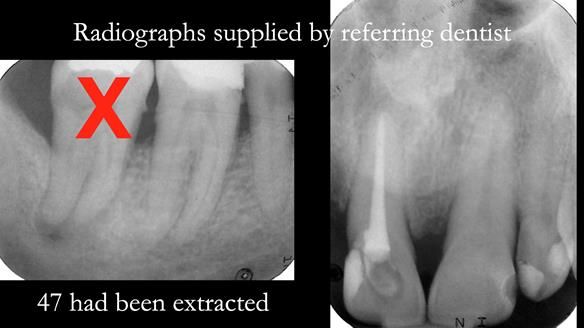

Case Overview: Brian was referred to me for specialist prosthodontics by his general dentist.

- Bruxism: The upper and lower teeth are worn and chipped due to heavy clenching and grinding. With a powerful bite and limited space for replacement teeth, dental implants supported fixed teeth are not recommended. A simpler solution is a metal-based partial denture/splint (“Combat denture”) as planned below. This will act as a splint to protect and replace the missing teeth.

- Restored Teeth: The remaining upper teeth and lower back teeth have large fillings and crowns, making them structurally weak. The new denture will reduce the forces on these teeth to help them last longer, though they may still require new restorations or extractions occasionally.

Treatment Process: I provided the clinical work, while Rowan Garstang handled the technical work. The treatment required five visits to fit the RPD. The worn lower anterior teeth were then built up. Unfortunately, I did not check the guidance on the denture teeth after this, and tooth 11 fractured off the denture. Brian was very understanding, and I adjusted the denture thoroughly. It has been fracture-resistant and trouble-free for the last three years.